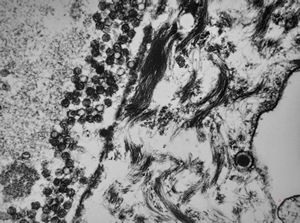

chylomicrons … negative staining